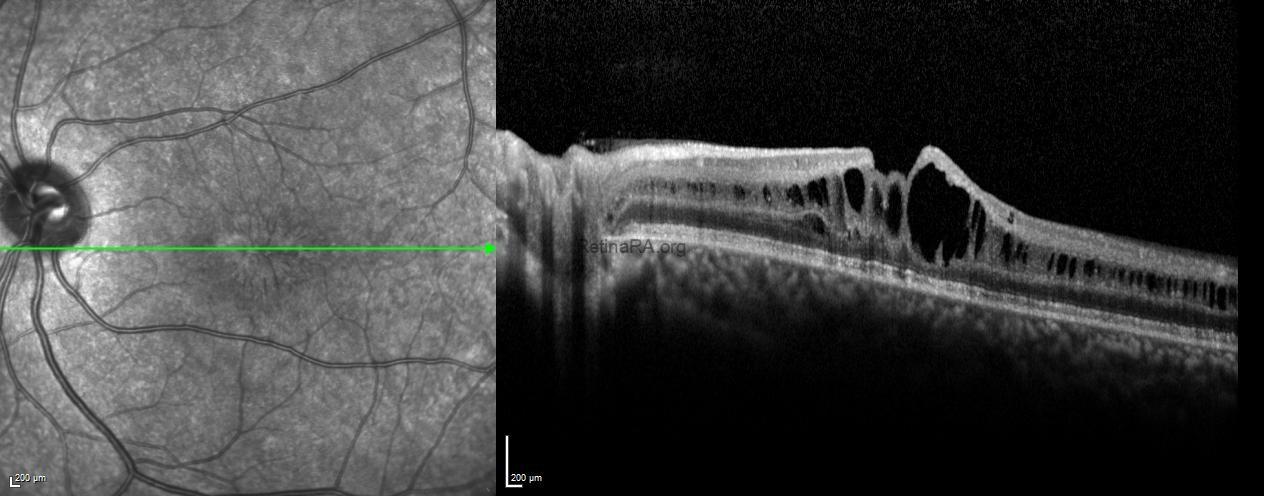

Optical coherence tomography (OCT) revealed diffuse cystoid spaces extending toward the optic nerve, causing splitting within the inner nuclear layer.

Fundus autofluorescence of the left eye showed alternating hyper- and hypoautofluorescent areas corresponding to the spoke-wheel pattern.